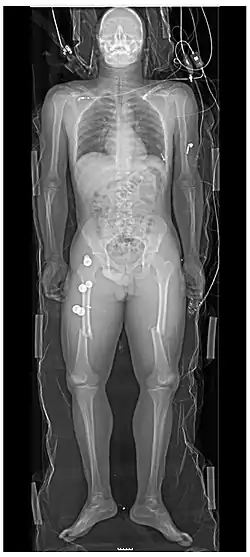

Persons with major trauma commonly have chest and pelvic x-rays taken,[6] and, depending on the mechanism of injury and presentation, a focused assessment with sonography for trauma (FAST) exam to check for internal bleeding. For those with relatively stable blood pressure, heart rate, and sufficient oxygenation, CT scans are useful.[6][25] Full-body CT scans, known as pan-scans, improve the survival rate of those who have suffered major trauma.[26][27] These scans use intravenous injections for the radiocontrast agent, but not oral administration.[28] There are concerns that intravenous contrast administration in trauma situations without confirming adequate renal function may cause damage to kidneys, but this does not appear to be significant.[25]

In the U.S., CT or MRI scans are performed on 15% of those with trauma in emergency departments.[29] Where blood pressure is low or the heart rate is increased—likely from bleeding in the abdomen—immediate surgery bypassing a CT scan is recommended.[30] Modern 64-slice CT scans are able to rule out, with a high degree of accuracy, significant injuries to the neck following blunt trauma.[31]